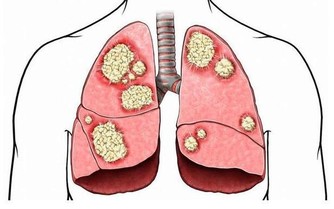

胰臟脂肪過多 可能導致糖尿病

第二型糖尿病可能是胰臟累積過多脂肪所造成的,

適度減少脂肪量,病症也會跟著改善。

胰臟位於胃的後方,

負責分泌胰島素以維持血糖穩定。

第二型糖尿病患者的胰島素分泌不足,

而且無法正常發揮功能。